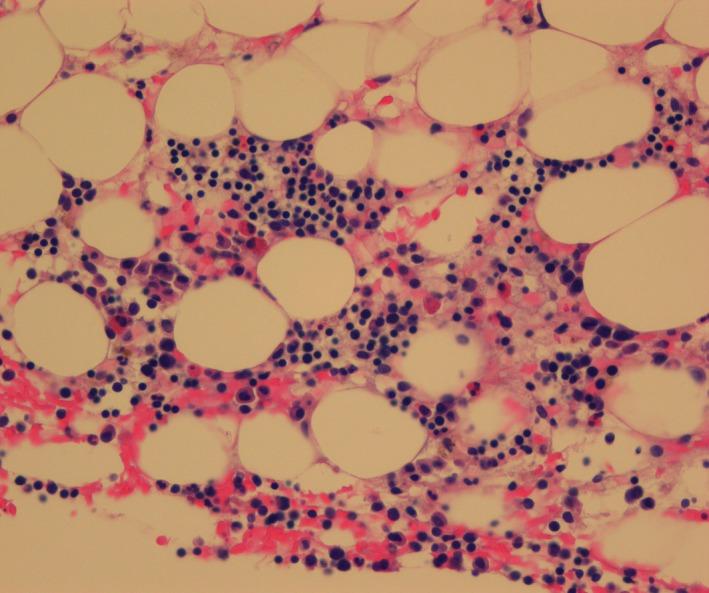

Hypoplastic acute myeloid leukemia (AML) is a rare variant of AML that mainly affects the elderly and accounts for 5%-7% of de novo AML. Prognosis for this disease is poor, and there is no standard therapy. We have treated an elderly patient with hypoplastic AML with low-dose prednisone and G-CSF with good results. We propose that this treatment may be a viable alternative to supportive therapy alone, or the tenuous chemotherapeutic challenge to elderly patients with hypoplastic AML.

Hypoplastic acute myeloid leukemia in an elderly patient. A long-term partial remission with low-dose prednisone and G-CSF.